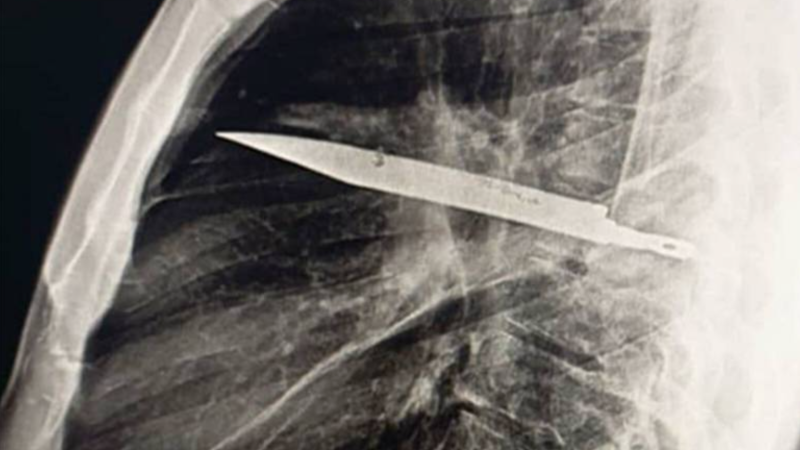

Tragédie v litoměřické porodnici: Lékaři oživovali čtyři novorozence, dva zemřeli

Vyhlášená porodnice v Litoměřicích, do které jezdí rodit matky z celé republiky, prošetřuje mimořádné události. Podle informací CNN Prima NEWS na tamním Centru porodní asistence...

Smrt novorozenců v litoměřické nemocnici vyšetřuje policie. O život měla bojovat i rodička

Tragické události v litoměřické porodnici, kde lékaři během 24 hodin resuscitovali při porodech čtyři novorozence, z nichž dva nakonec zemřeli, již šetří policie. Podle ní...

Tragédie v litoměřické porodnici: Během dne lékaři oživovali čtyři novorozence, dva zemřeli